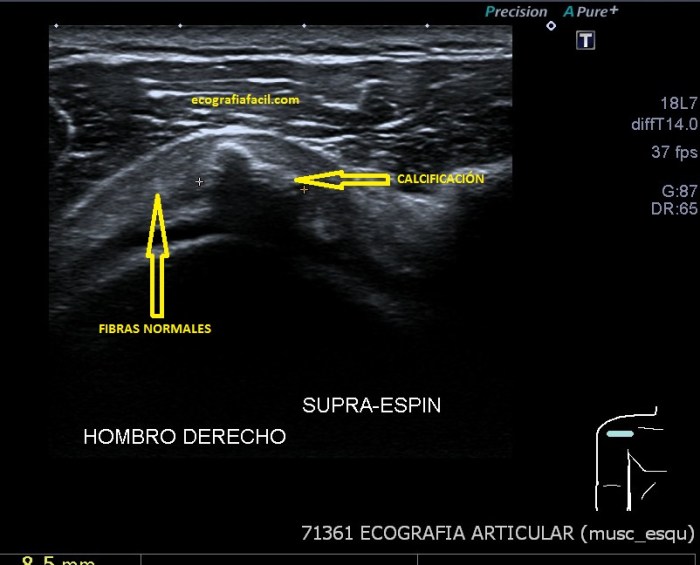

Si tu lo quieres estudiar en un corte transverso o eje corto del tendón verás como muestra de normalidad la imagen número 1. Semiológicamente es muy agradecido. Ves el tendón ovalado, hiperecogénico reposado en la corredera bicipital. El ligamento transverso humeral, hiperecogénico y lineal, anterior a la estructura tendinosa que descansa en la corredera.